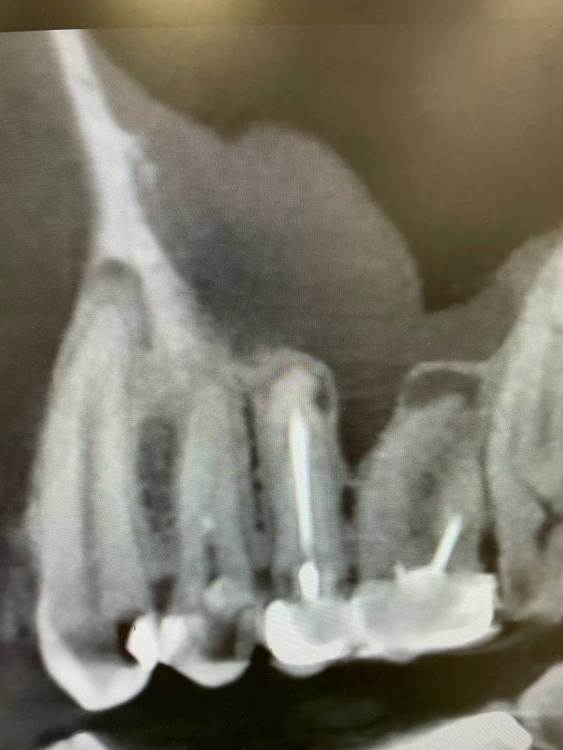

1586Doc Опубликовано 25 октября, 2021 Автор Поделиться Опубликовано 25 октября, 2021 Вот такой красавчик 46:) 1 1 Ссылка на комментарий